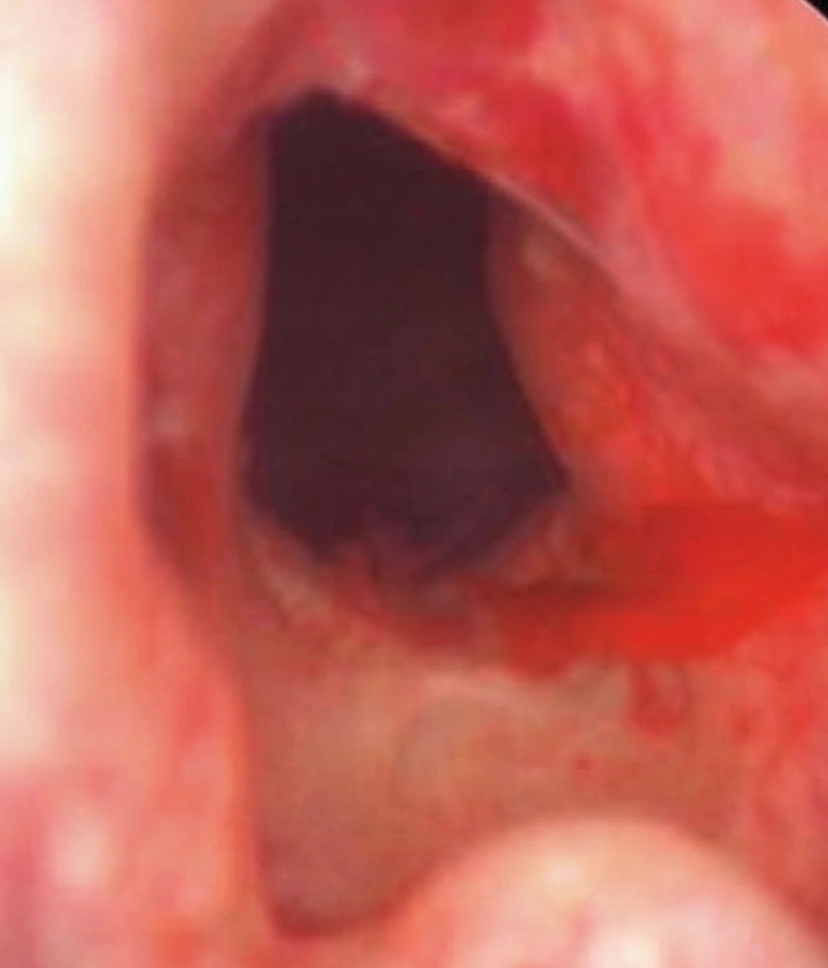

(하루 3~4회 소변줄을 자가로 넣어 소변 배출) - 방광경소견

- 전립선 용적 : 50cc

- 거대한 게실(600cc) 관찰되어 방광용적 600cc로 전체 방광용적 1200cc 소견

전립선종염 및 양측 비대로 인한 폐색 소견 관찰됨